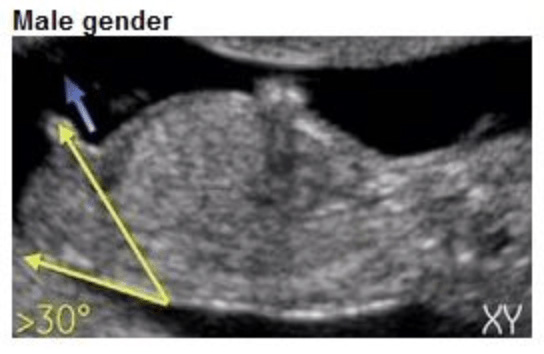

Het verschil? De hoek. Bij een jongen staat de nub in een hoek van meer dan 30 graden ten opzichte van de ruggengraat. Bij een meisje ligt de nub meer horizontaal, evenwijdig aan de ruggengraat.

• Bij een jongen: de nub begint omhoog te wijzen, in een hoek van 30 graden of meer ten opzichte van de ruggengraat. Hij groeit uit tot de penis.

• Jongen: zoek naar een nub die duidelijk omhoog wijst, in een hoek ten opzichte van de onderrug. Soms is er al een kleine verdikking zichtbaar aan het uiteinde.

Echo met nub in hoek van 30+ graden, kenmerkend voor een jongen

Nub jongen (30°+)

• Meer dan 30 graden omhoog? Waarschijnlijk een jongen